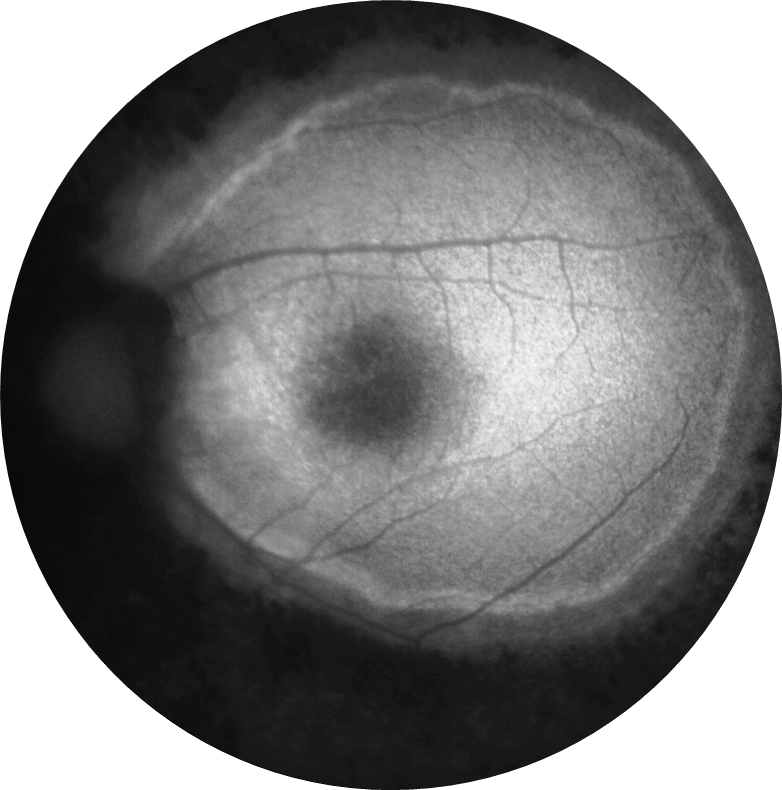

Kliniğimize her iki gözde çocuk yaştan bu yana gittikçe artan görme azlığı şikayetiyle 29 ve 21 yaşındaki iki kardeş başvurmuştur. 29 yaşındaki kardeşin her iki gözde görme keskinliği 3 mps düzeyinde iken 21 yaşındaki kardeşin 0,2 düzeyindedir. Hastaların her iki göz fundus otofloresans görüntülerini görmektesiniz. Bu bulgulara göre tanınız nedir? Lütfen cevabınızı aşağıya yazınız.

Bu ay size her iki gözde çocuk yaştan bu yana gittikçe artan görme azlığı şikayeti olan 29 ve 21 yaşındaki iki kardeşin fundus otofloresans görüntüleri eşliğinde tanılarını sormuştuk.

Tanı: Retinitis pigmentosa ’dır.

RP hastalarında, otofloresan görüntülemede zamanla daralan ve hastalık ilerlemesinin bir belirteci olarak hareket eden bir hiperotofloresan halka ortaya çıkabilmektedir. Bu halkanın dış sınırının içindeki fotoreseptöre atfedilen katmanların nispeten korunduğu, halkanın dış sınırının dışında ise elipsoid bölge ve dış limitan membran kaybı ile fotoreseptör katmanlarının incelmesi ve dış nükleer katmanın incelmesi veya yokluğu gözlemlenebilmektedir.